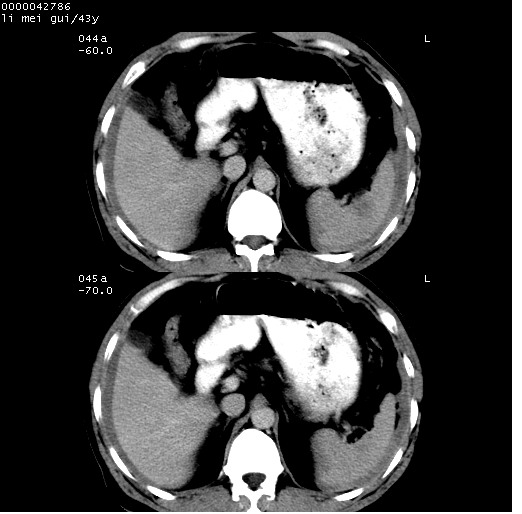

| 患者,男,43岁。突发腹痛2小时,面色苍白,难以平卧。自述近期无明确外伤史,为摩托车驾驶员。 腹部b超检查:脾脏中上极回声异常,肿瘤待排。 临床诊断:腹痛原因待查。 上中腹部ct轴位平扫+增强扫描(层厚10mm,螺距1.0,重建间隔10mm),图像如下: ![]() ![]() ![]() ![]() ![]() ![]() ![]() ![]() ![]() ![]() ![]() ![]() ![]() ![]() ![]() ![]() ![]() ![]() ![]() ![]() ![]() ![]() ![]() ![]() ![]() ![]() ![]() ![]() ![]() ![]() ![]() ![]() ![]() ![]() ![]() zrs发言:支持脾破裂 wwp发言:支持脾破裂并腹水。 xulianj发言:脾脏肿瘤破裂可能性大 zsl6918发言:不像肿瘤出血,考虑还是与外伤后引起的慢性出血有关 zzyy发言:平扫见肝周及脾周积液,脾内密度不均。脾内肿瘤较少见。还是外伤性脾破裂。 沈丘东方医院发言:脾门区一个不均匀强化病灶与其周液体相连多考虑脾占位破裂出血 yixianman001011发言:脾破裂并腹水是可以肯定的,具体原因多以肿瘤性破裂出血,脾脏淋巴瘤可能性大. 结果: 术后,经详细询问患者,其仔细回忆:一月前骑摩托时左侧腰部与别人有“轻微”触碰,因责任在自已,当时又无明显不适,未引起注意。 临床术后诊断:脾破裂并失血性休克(1.外伤性迟发性脾破裂。2.脾脏肿瘤破裂?) 术后标本病检:脾破裂并出血,未见明显肿瘤成份。 原贴地址:http://www.radinet.com.cn/forum_view.asp?forum_id=4&view_id=34070 |